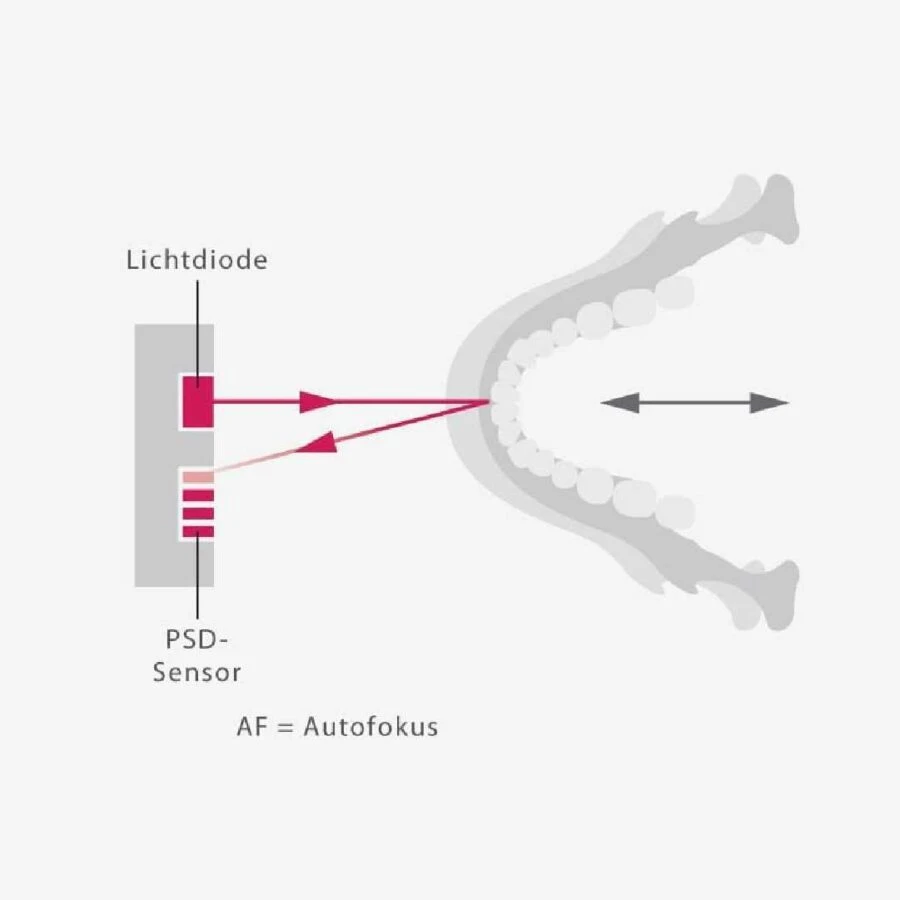

Tự động định vị AF

– Định vị 3D dễ dàng với 5 chùm tia laser: cho phép sự linh hoạt khi định vị theo các cách khác nhau.